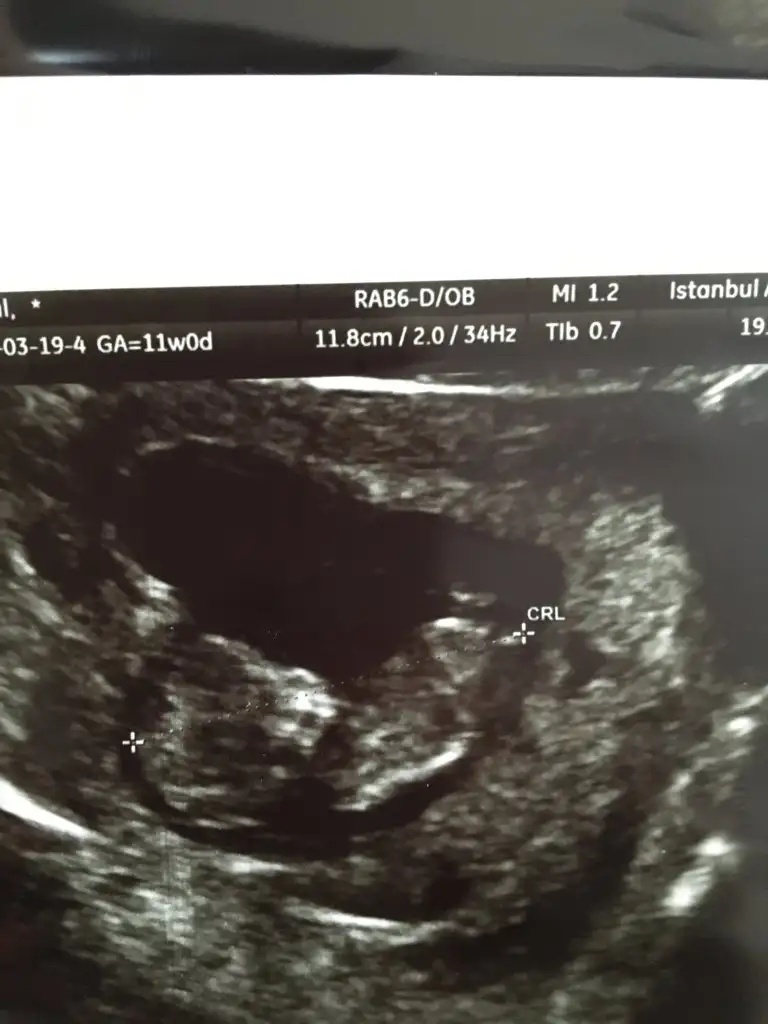

Acil e gittik . 8 haftama bugun girmistm ve karindan ultroson ile goremediler birsey . Bhcg seviyem 17.862 cikti .

Yarin sabah ( burada pazar sabahi olucak ) vajibal ultrosona alicaklar ama doktor buyuk ihtimalle dusuk dedi ..